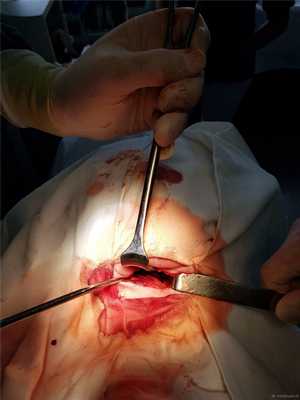

Доступ к С2 под нижней челюстью справа. Можно и слева, но правше и сподручнее справа.

Затем под рентгеновским контролем устанавливается спица в необходимой точке ввода под нужную траекторию.